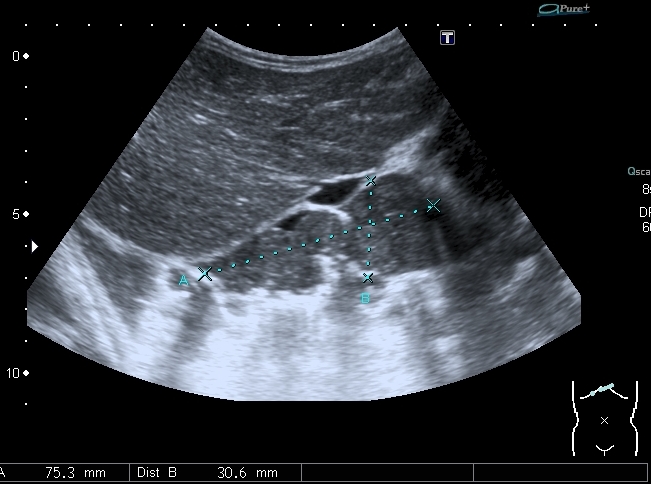

Предлагаю интересные изображения, полученные при сканировании лёгких через межрёберные промежутки и печень у ребёнка 4-х лет с подозрением на пневмонию

Согласен в отношении нижней доли правого лёгкого, изменения в ней похожи на сливную инфильтрацию при пневмонии, хотя носят несколько многоузловой характер. Но то что мы видим со спины в левом лёгком на пневмоническую инфильтрацию не похоже.

Добавляю сканы печени, я думаю они являются хорошей подсказкой о природе изменений в лёгких

ЦДК образований в лёгких не делал, если быть откровенным, порядок находок у этого пациента был следующим: МТС в печени - изменения в нижней доле правого лёгкого - забрюшиное пространство - левая почка - левое лёгкое - правое лёгкое - рентген лёгких. Картина в комплексе была и так ясна, т.е. то, что это MTS сомнений не вызывало. Ну а после патогномоничной рентгеновской картины - вопросов тем более не было.